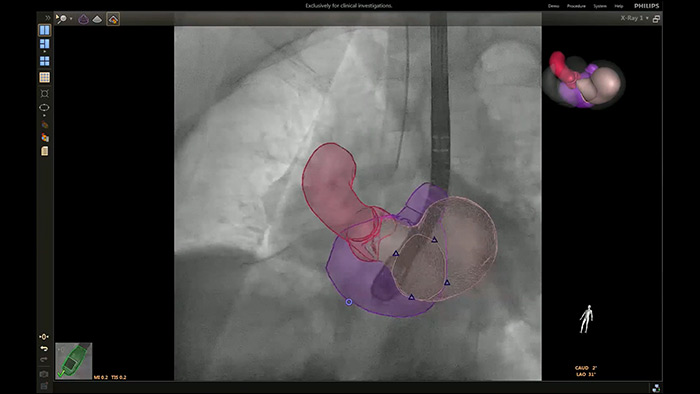

Implementación de la superposición de la ETE 3D en vivo de la oclusión de la LAA con EchoNavigator

Guía de punción transeptal mediante EchoNavigator